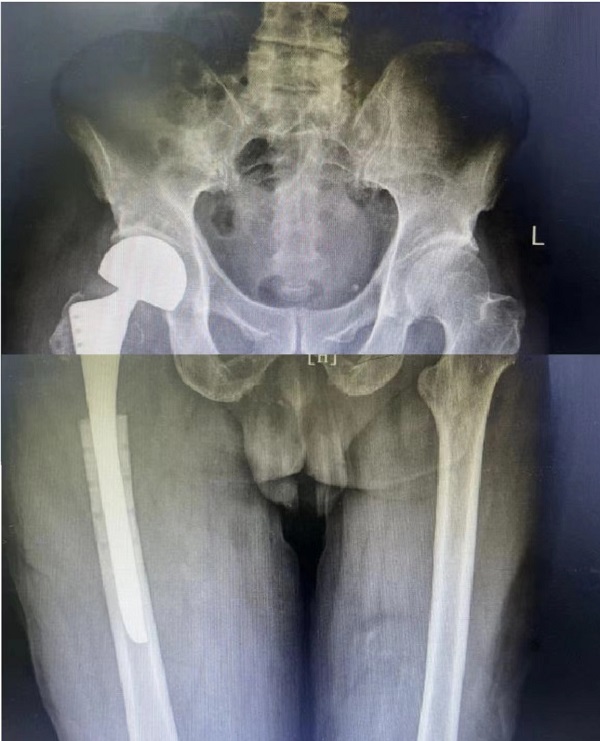

创伤骨科郭永良主任、王争刚主任医师仔细了解患者病史、查体阅片,和患者家属多次沟通,阐明各种治疗方案的优缺点,最终决定行右股骨近端内固定钢板及骨水泥取出、人工股骨头置换术。手术由郭永良主任亲自主刀、在王争刚主任医师等辅助下进行,历时1.5小时顺利完成。现术后3周,患者髋关节功能恢复良好,可扶拐下地活动。

术后X片: